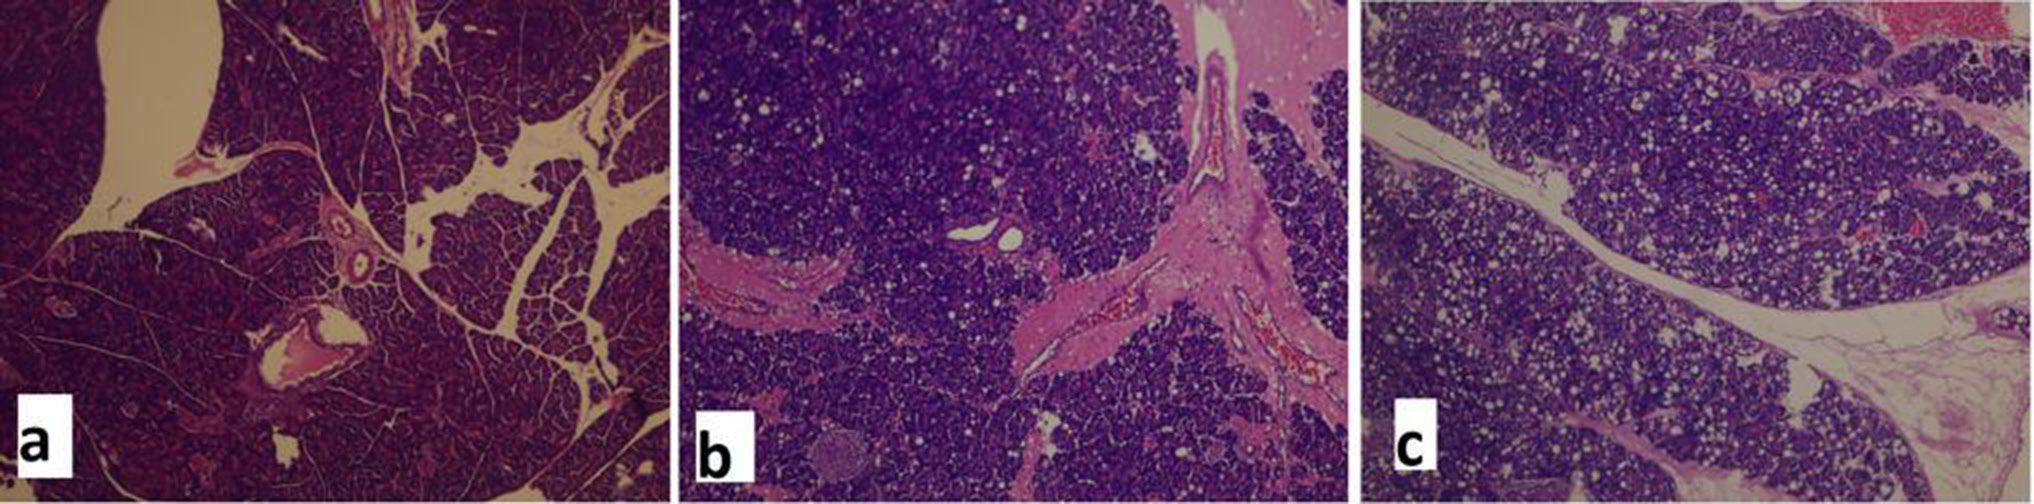

Laparotomy was performed by midline incision following decapitation, and pancreatic tissue was excised for histopathological assessment. Specimens were placed in 10% formaldehyde and delivered to the pathology laboratory. Tissue sections were stained using hematoxylin and eosin (H&E) and then investigated (Figure 1, Figure 2). Edema, inflammation, localization, and necrosis were scored between 0 and 4 using the Schonberg index.11